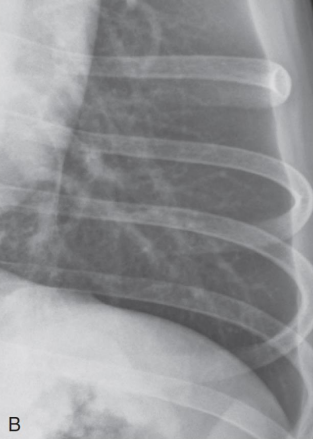

VS.

(왼쪽이 정상, 말단으로 갈수록 깨끗. 말단에도 tram line 보이는 오른쪽은 비정상.)

흰색: doughnuts, 검은색: trams)

Lobar sign

alverolar pattern이 한 엽에만 진하고 뚜렷하게 나타났을 때.

흰색 부분에 alveolar pattern 뚜렷

Alveolar pattern

- 무기폐, 폐렴,. .

- 생명과 관련 있는 질병과 밀접하여, 가장 중요